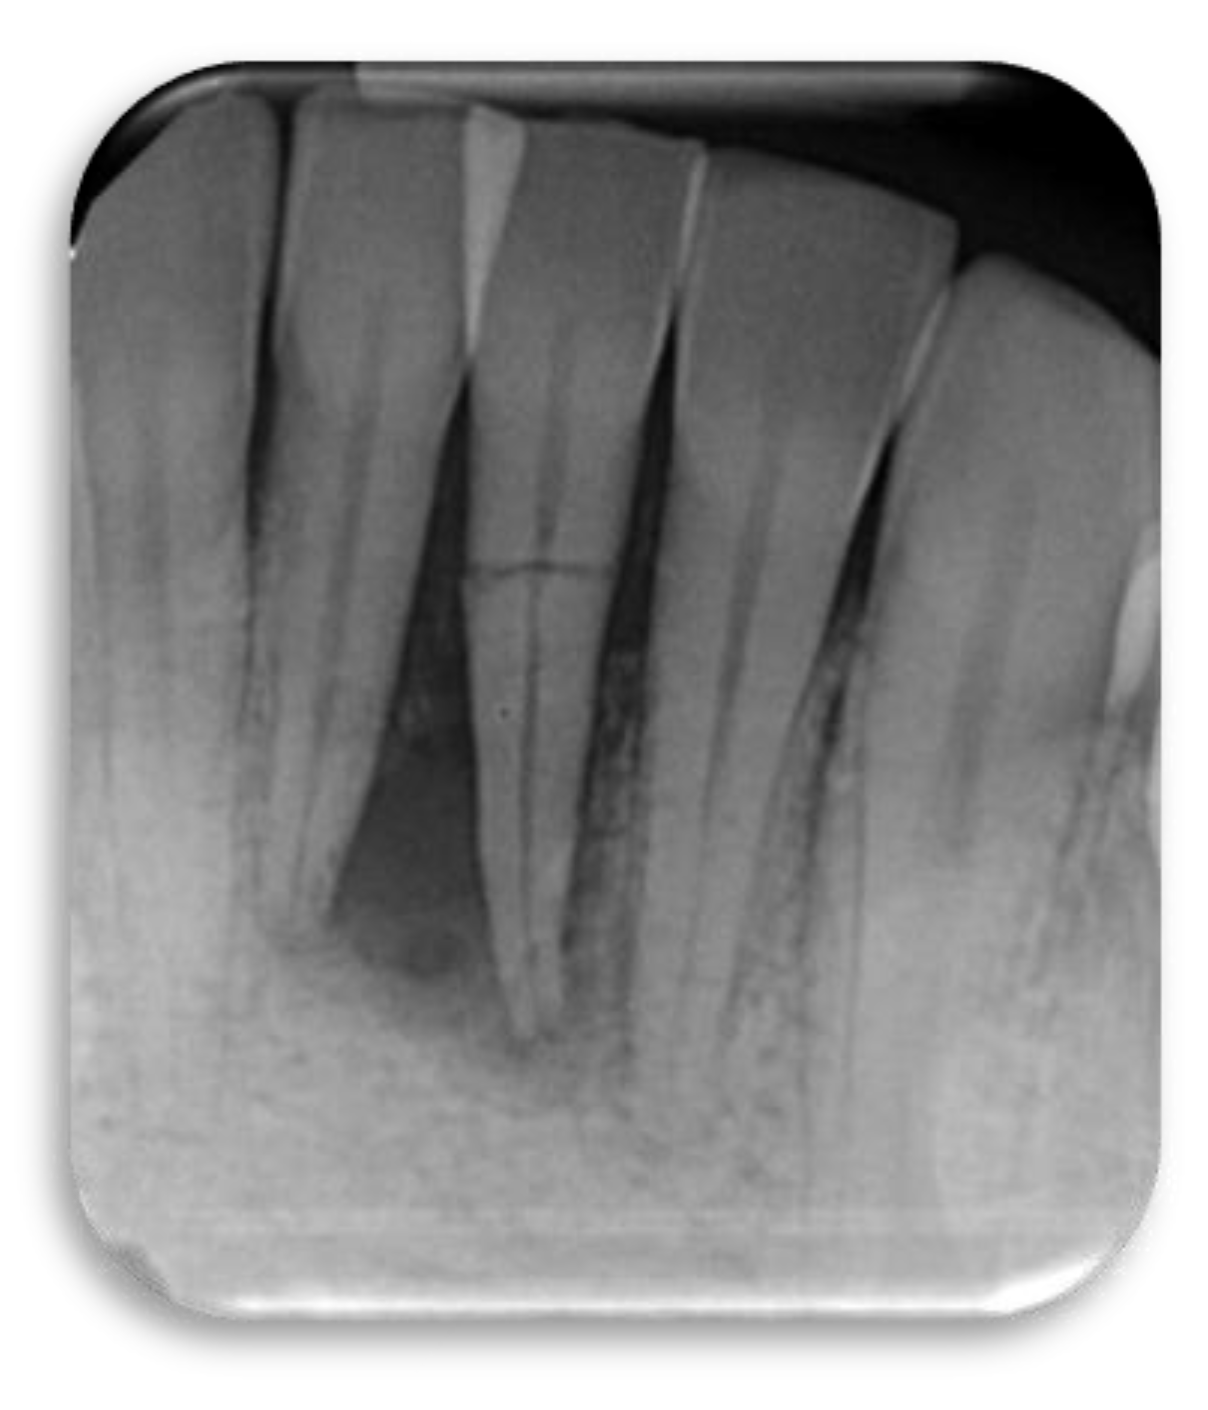

This radiograph shows tooth#24 horizontal fracture and radiolucency in the anterior mandible, as a result of a blow received from the patient playing boxing.